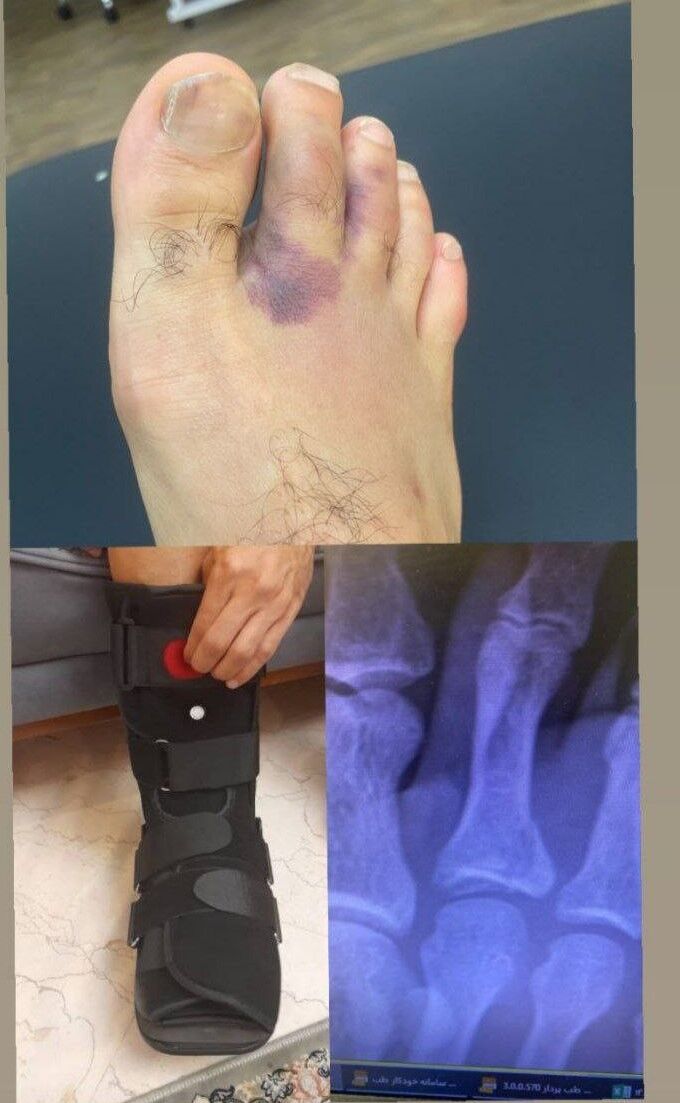

روزنو :با انتشار تصویری در فضای مجازی، شدت مصدومیت امید عالیشاه مشخص شد.

امید عالیشاه بدشانس‌ترین بازیکن پرسپولیس تا اینجای تمرینات پیش فصل بوده چرا که بر اثر برخورد با یکی از هم باشگاهی‌هایش باید مدتی نسبتا طولانی دور از تمرین باشد.

عالیشاه در بازی تدارکاتی با تیم منتخب آکادمی پرسپولیس آسیب دید و حالا نزدیک به یک هفته است که تمرین نمی‌کند اما شاید این دور بودنش از تمرین سه هفته دیگر هم طول بکشد.

پس از انتشار خبر مصدومیت عالیشاه، این بازیکن روز گذشته در جریان دیدار دوستانه تیم های پرسپولیس و اکسین در ورزشگاه شهید کاظمی با آتل حضور پیدا کرد و بازی هم تیمی‌هایش را از نزدیک تماشا کرد.

امروز عکسی از شکستگی پای عالیشاه منتشر شد که نشان می دهد انگشت پای این بازیکن شکسته و قادر به همراهی تیم پرسپولیس نخواهد بود.